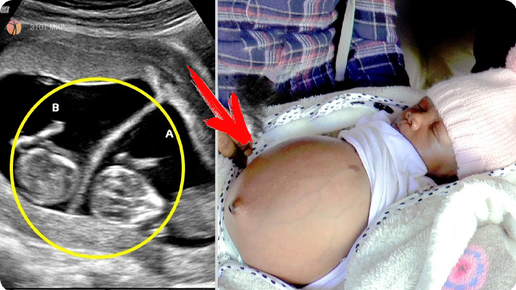

Родилась девочка, беременная близнецами, и врачи были в полном оцепенении